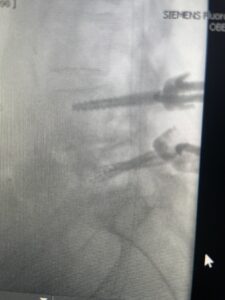

Another patient is a 62 year-old female with progressive low back pain and right leg pain and numbness that radiates to the top of her foot. She tried physical therapy and epidural injections. MRI demonstrated severe L3-4 stenosis and a grade 1 spondylolisthesis (Fig 4). There was L5-S1 and L4-5 disc collapse with modic end-plate changes. Biomechanically because of the significant degeneration of these disc spaces which stiffened the L4-S1 segment more stress was placed on the L3-4 segment, resulting in significant premature degeneration and compensatory stenosis and segmental instability. The MRI also showed pathologically, because of the slip, the L3 inferior processes were more anteriorly oriented and hence contributing to the majority of the lumbar canal compromise. Note the more sagittally-oriented facets in this case compared to the prior case (Fig 5). The patient underwent a decompressive laminectomy with attention of removing the inferior processes of L3 to fully decompress the canal. We also performed an L3-4 fusion with instrumentation (Fig 6). The patient had an uneventful postoperative course with improvement of leg pain. Of note with relief of the disabling leg pain patients are generally very happy. Patients can often manage their low back pain; it is the leg pain that they just can’t tolerate.

Fig 6: AP and lateral fluoroscopic images demonstrating pedicle screw placement in L3-4 fusion for spondylolisthesis.